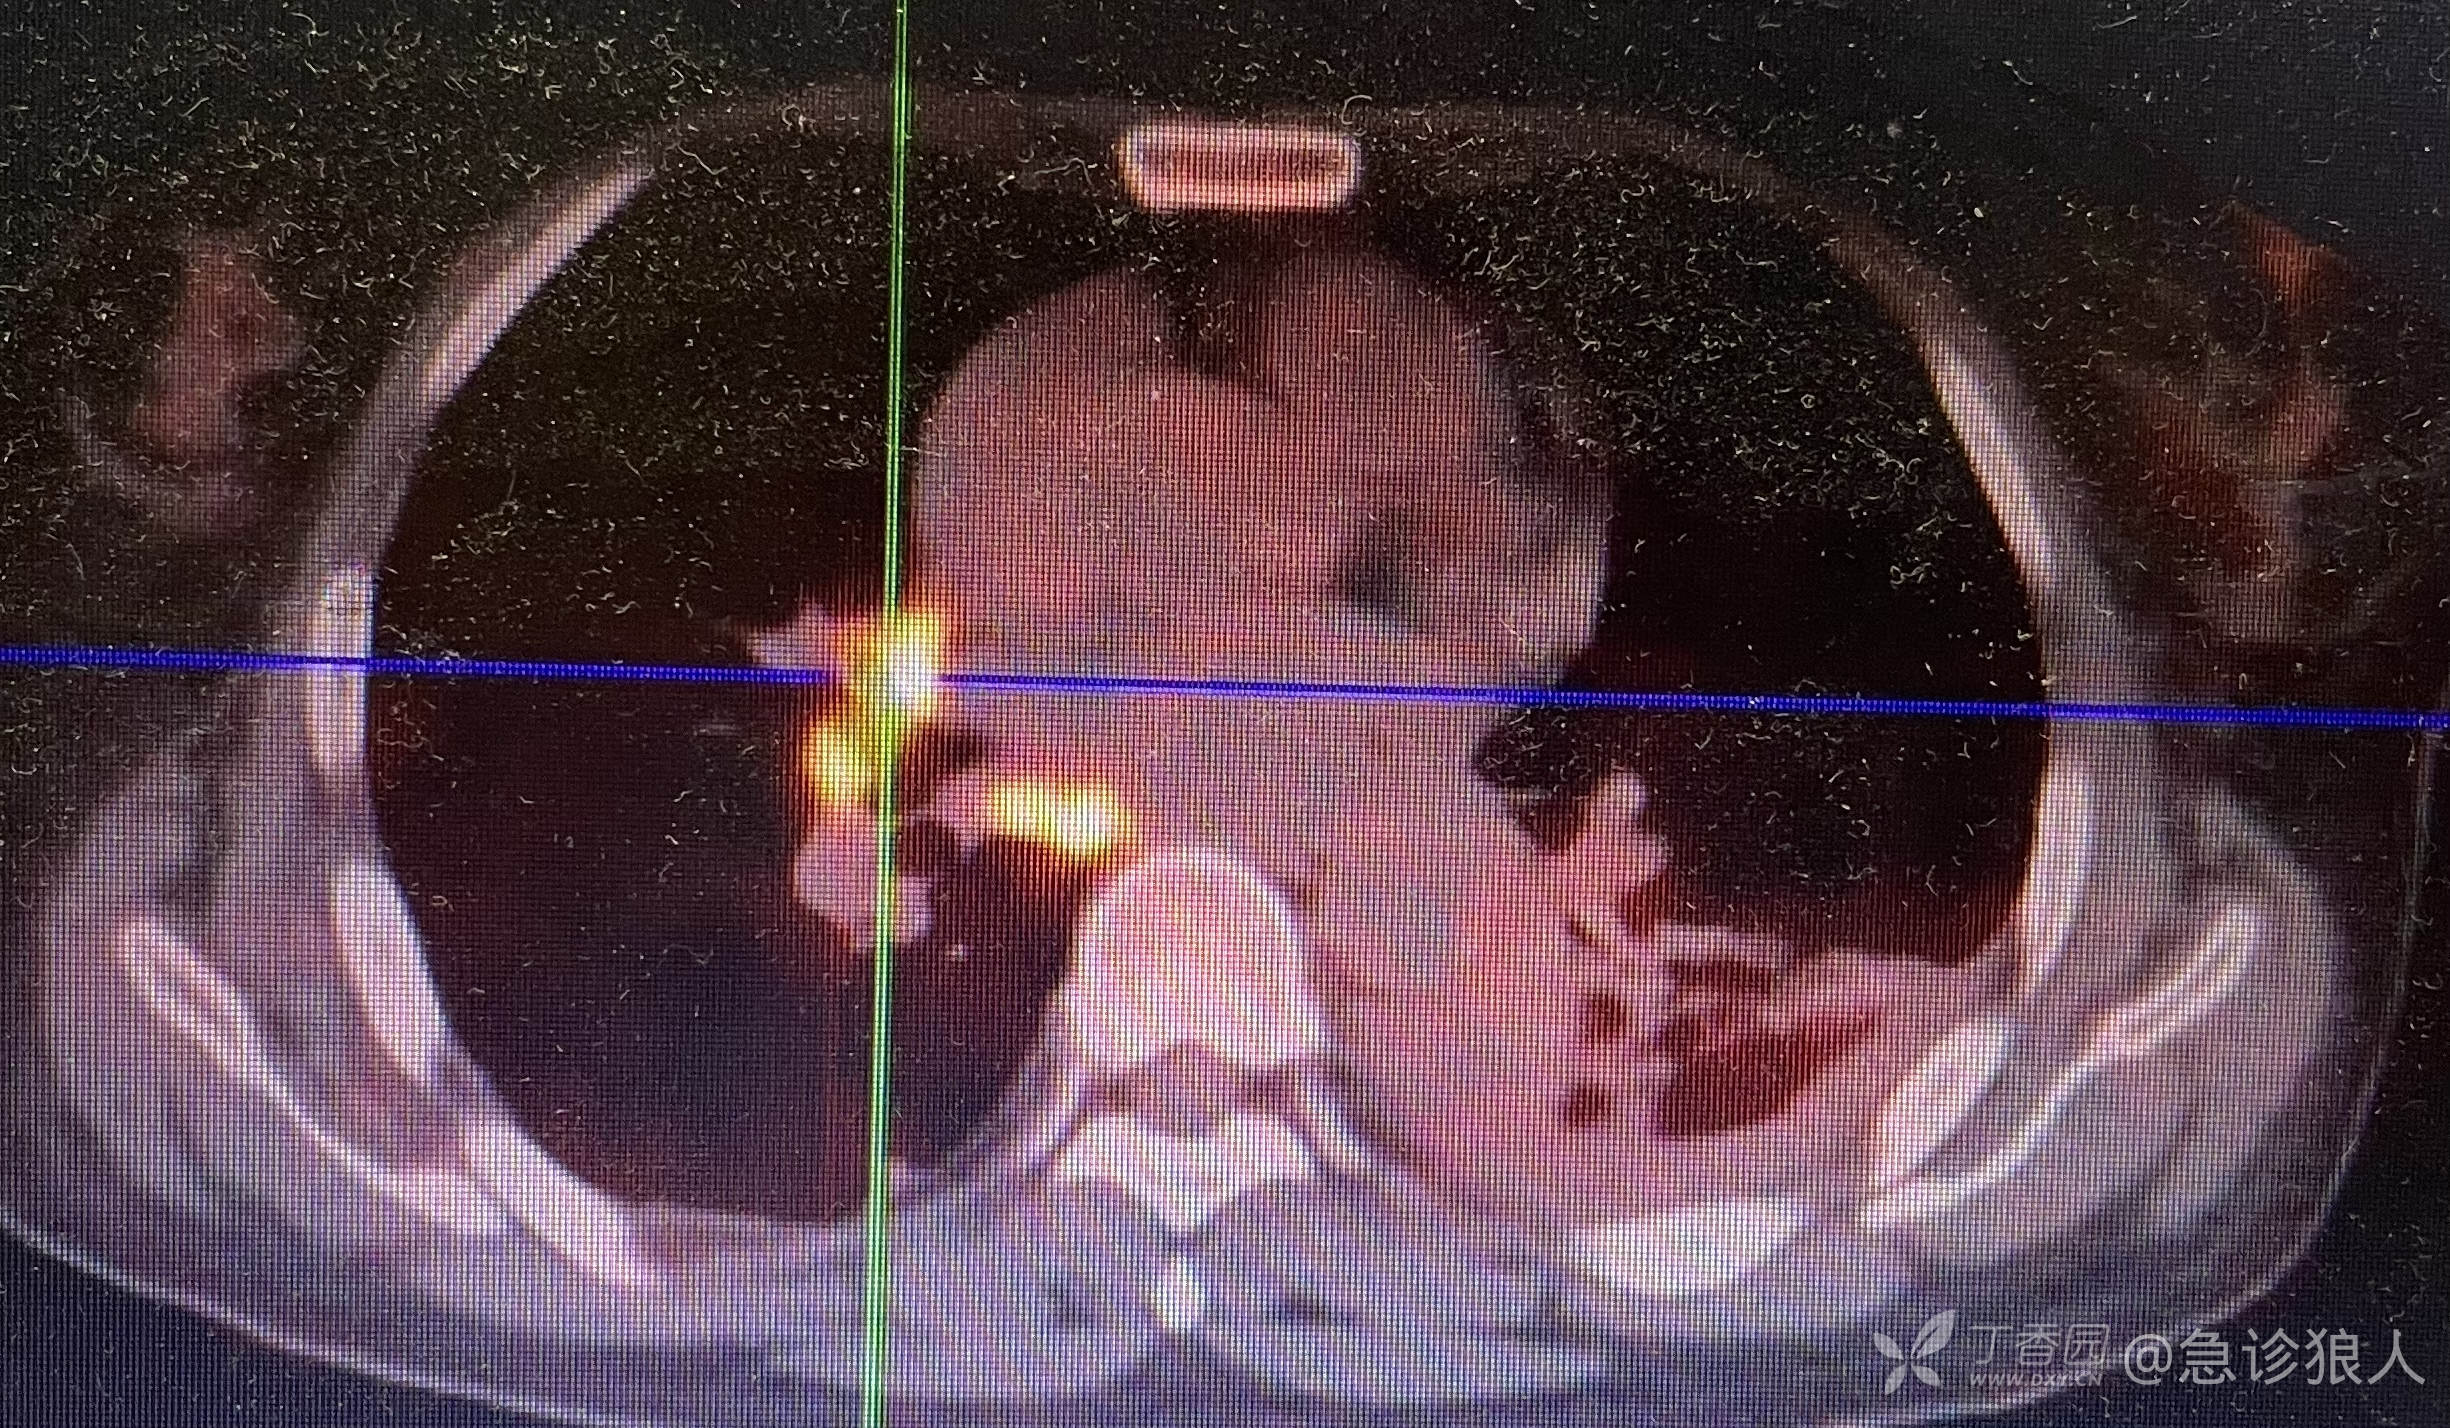

又反复看了Ct,恍然大悟,立刻给家属谈话,家属同意PET- C T。

如下:

哎!

是不是很漂亮!

病人家属看完结果,放弃治疗回家!

问题是,为什么这么小的一点,就能导致这么大范围的扩散?